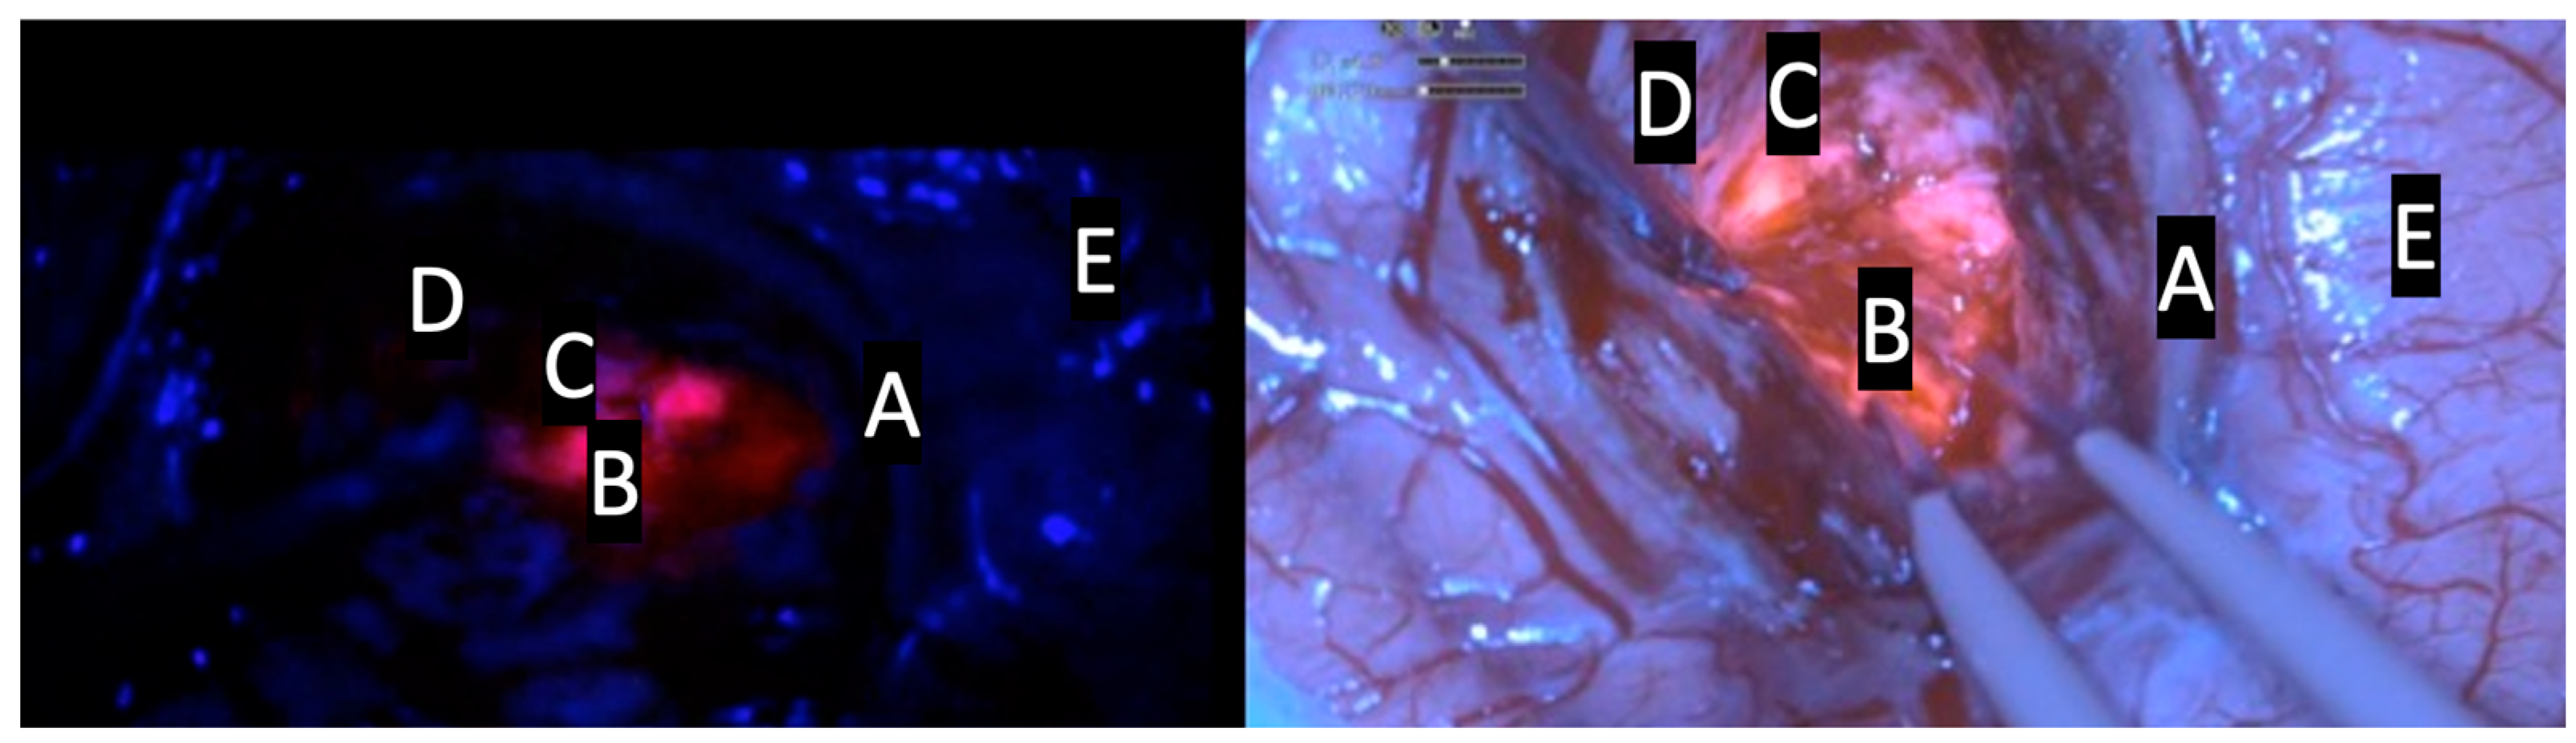

| Intensity of Fluorescence | Type of Tissue |

|---|---|

| Intense red or lava-like | Tumor |

| Faint pink or pinkish | Infiltrating tumor cells |

| Blue | Normal tissue |